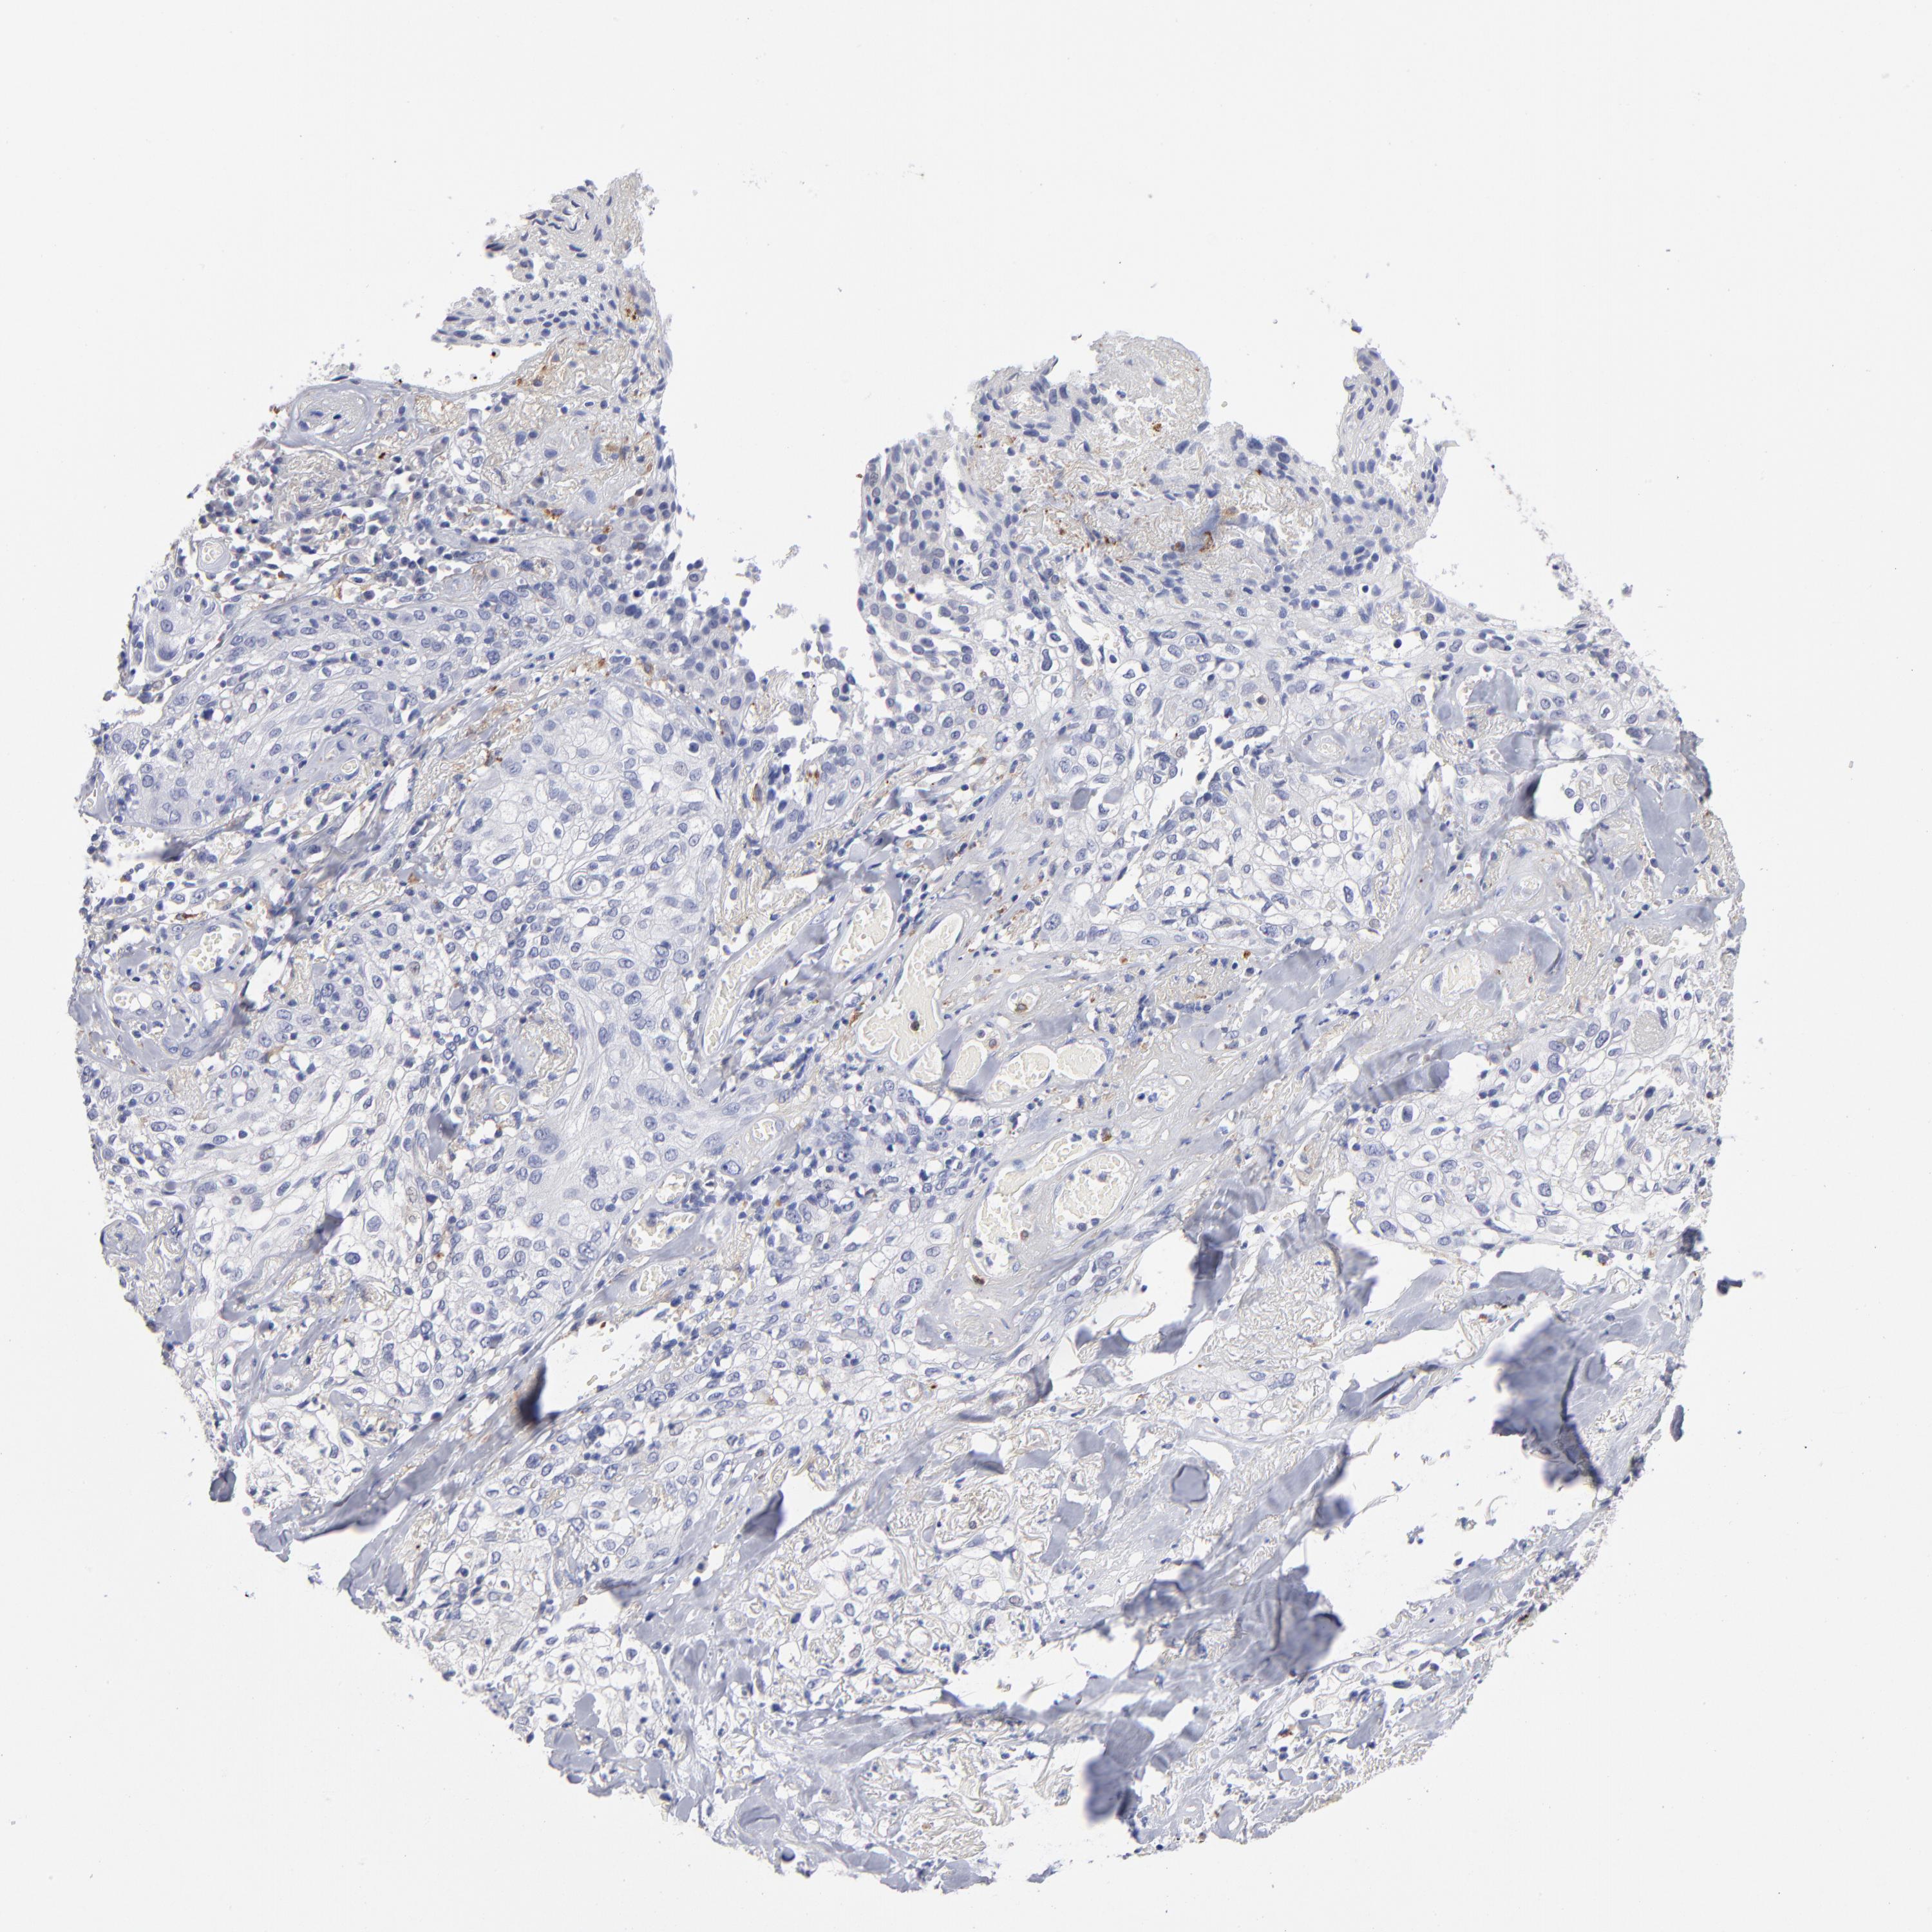

SKIN CANCER - Protein expressioni

A mouse-over function shows sample information and annotation data. Click on an image to view it in a full screen mode. Samples can be filtered based on level of antibody staining by selecting one or several of the following categories: high, medium, low and not detected. The assay and annotation is described here.

Antibody stainingi

Antibody staining in the annotated cell types in the current human tissue is reported as not detected, low, medium, or high, based on conventional immunohistochemistry profiling in selected tissues. This score is based on the combination of the staining intensity and fraction of stained cells.

Each image is clickable and will lead to virtual microscopy that enables deeper exploration of all samples and also displays staining intensity scores, fraction scores and subcellular localization as well as patient and tissue information for each sample.

Antibody HPA003740

Squamous cell carcinoma, NOS

Basal cell carcinoma